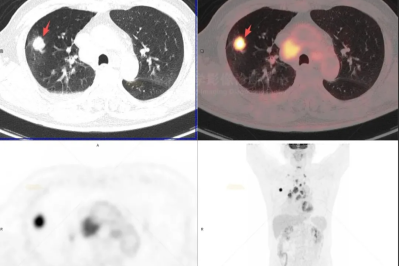

【高尚病例】巨大硬化性肺细胞瘤 1 例

【高尚病例】PET/CT 发现肋骨孤立性浆细胞瘤 1 例

18F-FDG PET/CT 显像在乳腺外 Paget 病诊疗中的关键作用